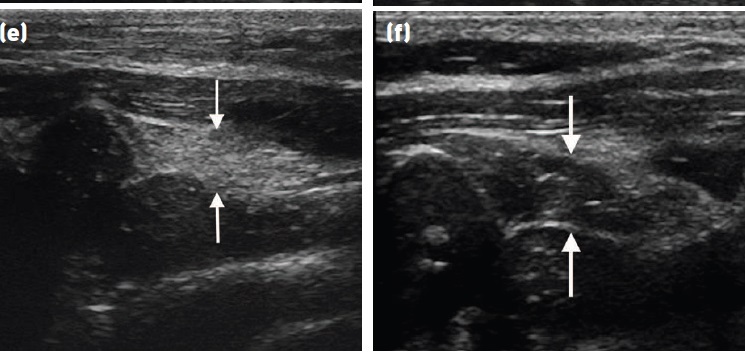

Fig 8: Comparison of echogenicity of the cricoarytenoideus lateralis and vocalis (arrows)

and cricoarytenoideus dorsalis (arrowheads) musculature. Horses with recurrent

laryngeal neuropathy have increased echogenicity and more homogeneous echogenicity

of the cricoarytenoideus lateralis and cricoarytenoideus dorsalis muscles. Dorsal plane

ultrasound images of the cricoarytenoideus lateralis muscle of (a) a horse with recurrent

laryngeal neuropathy and (b) a normal horse. Transverse plane ultrasound images of the

cricoarytenoideus lateralis and vocalis muscles of (c) a horse with recurrent laryngeal

neuropathy and (d) a normal horse. Dorsal plane ultrasound images of the cricoarytenoideus

dorsalis muscle of (e) a horse with recurrent laryngeal neuropathy and (f) a normal horse. In

the dorsal plane images, rostral is to the left and caudal is to the right and in the transverse

plane images, dorsal is to the left of the image and ventral is to the right